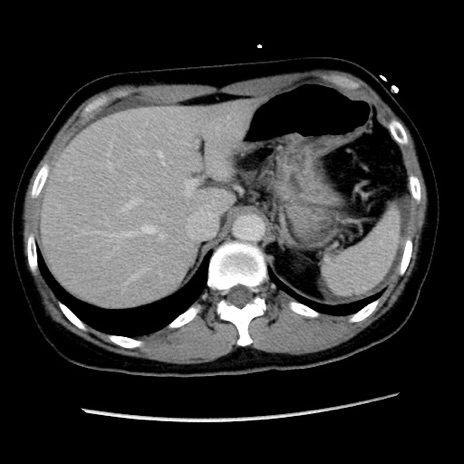

症例10(横断像)

【症例】 50歳代女性

【主訴】 腹痛

【現病歴】前日生レバーを食べた。今朝に排便あり。 昼前に突然発症の腹痛を生じ、当院救急外来を受診した。

【既往歴】 子宮筋腫にてで子宮全摘後

【身体所見】 意識清明、腹部:平坦、軟、下腹部やや左を中心に圧痛・反跳痛あり、筋性防御あり

【データ】WBC 7800、CRP 0.07